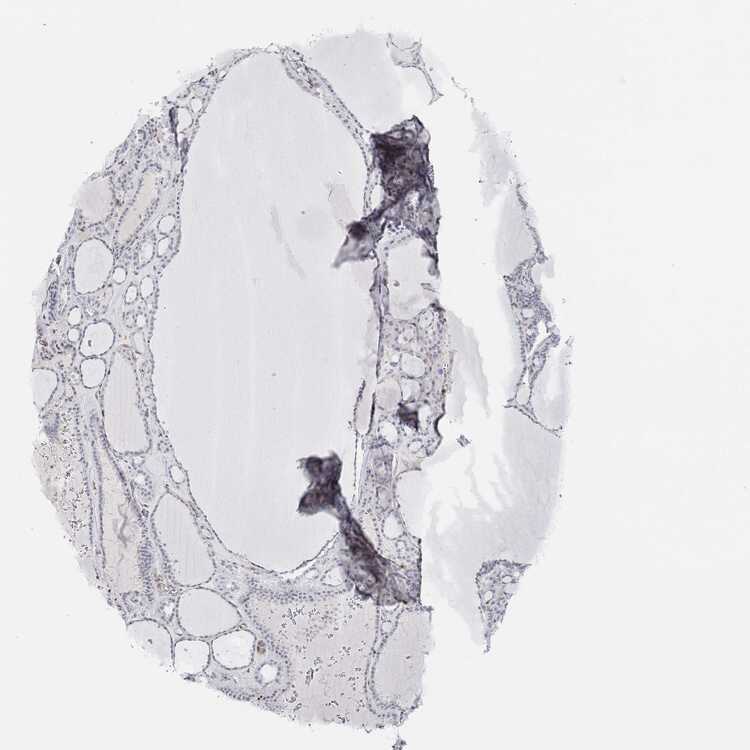

TISSUE PRIMARY DATA THYROID GLAND Show tissue menu

THYROID GLAND - Antibody stainingi

Antibody staining in the annotated cell types in the current human tissue is reported as not detected, low, medium, or high, based on conventional immunohistochemistry profiling in selected tissues. This score is based on the combination of the staining intensity and fraction of stained cells.

Each image is clickable and will lead to virtual microscopy that enables deeper exploration of all samples and also displays staining intensity scores, fraction scores and subcellular localization as well as patient and tissue information for each sample.

Antibody HPA001399Antibody HPA023884Antibody CAB004307Antibody CAB080432

Glandular cells Not detectedNot detectedNot detectedNot detected